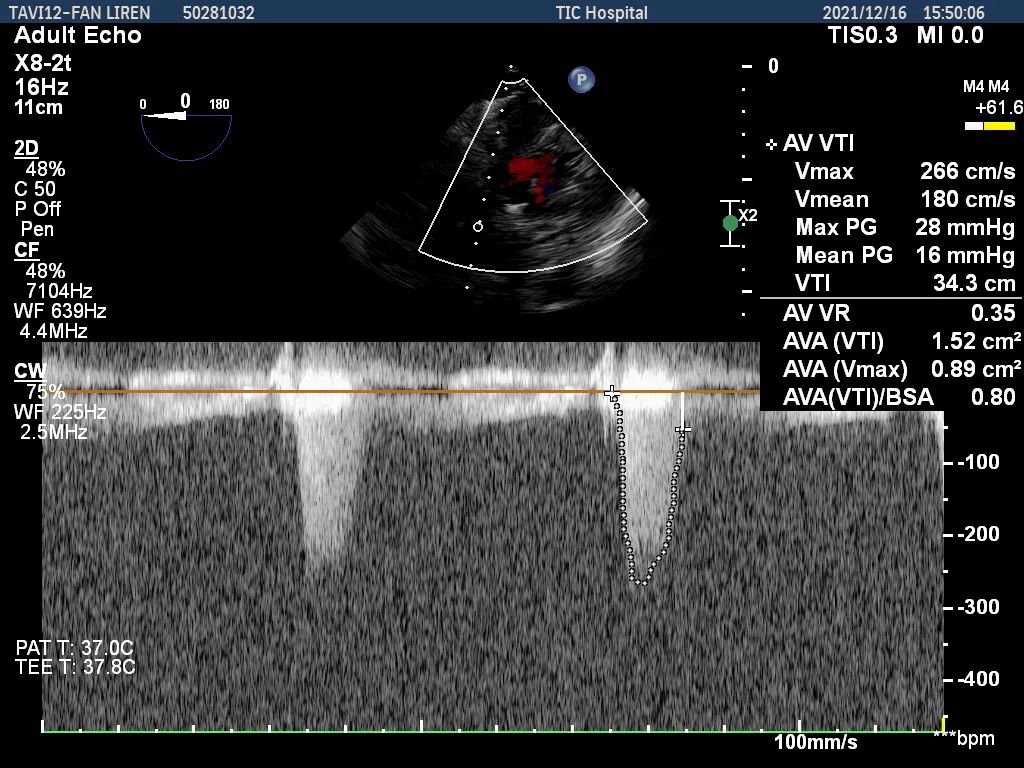

首都医科大学附属北京安贞医院老年心血管病中心由多学科管理团队组建,推行协同诊疗模式,实施心脏膜病的规范诊疗和长期管理,以最大程度提高心脏端股病患者的生存率和生活质量。本例患者术前经过影像科徐磊主任团队及心脏超声科张纯主任团队的精准评估和诊断,针对患者临床和解剖结构的诸多不利因素,周玉杰教授团队为患者制定了周全的手术方案。最终,周玉杰教授TAVR团队克服重重困难,成功为患者植入启明VenusA L23mm主动脉瓣膜,术后主动脉瓣口最大流速下降至2.66m/s,最大压差下降至16mmHg。再行主动脉造影提示瓣膜置入位置良好、形态完整,超声提示未见明显瓣周漏,瓣膜赘生物完全覆盖贴合至主动脉壁。围术期患者心率血压平稳,心律为窦性心律,未发生任何传导阻滞,双侧股动脉缝合良好,各穿刺点无渗血。在瓣膜植入后患者返回监护室出现持续性低血压,考虑发生自杀左心室现象,在持续补液及去甲肾上腺素、多巴胺泵入后患者血压逐渐回升,血流动力学稳定,患者无明显不适,手术圆满成功。